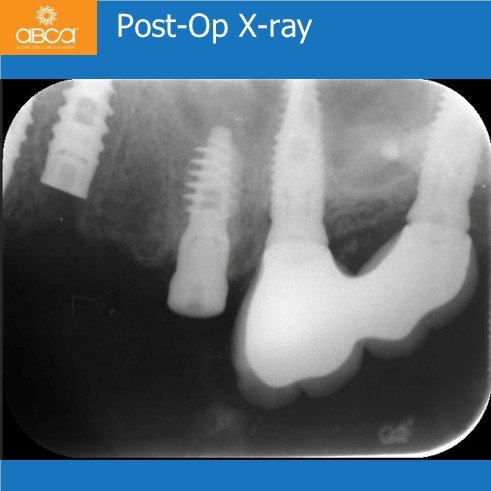

The clinician extracts the teeth and places immediate implants in sites #22 (10) and #23 (11). After performing a crestal sinus lift with Augma Bond Apatite®, the clinician placed a stable implant in site #25 (13).

Bond Apatite® also filled the wide socket at site #25 (13) to enhance implant stability.